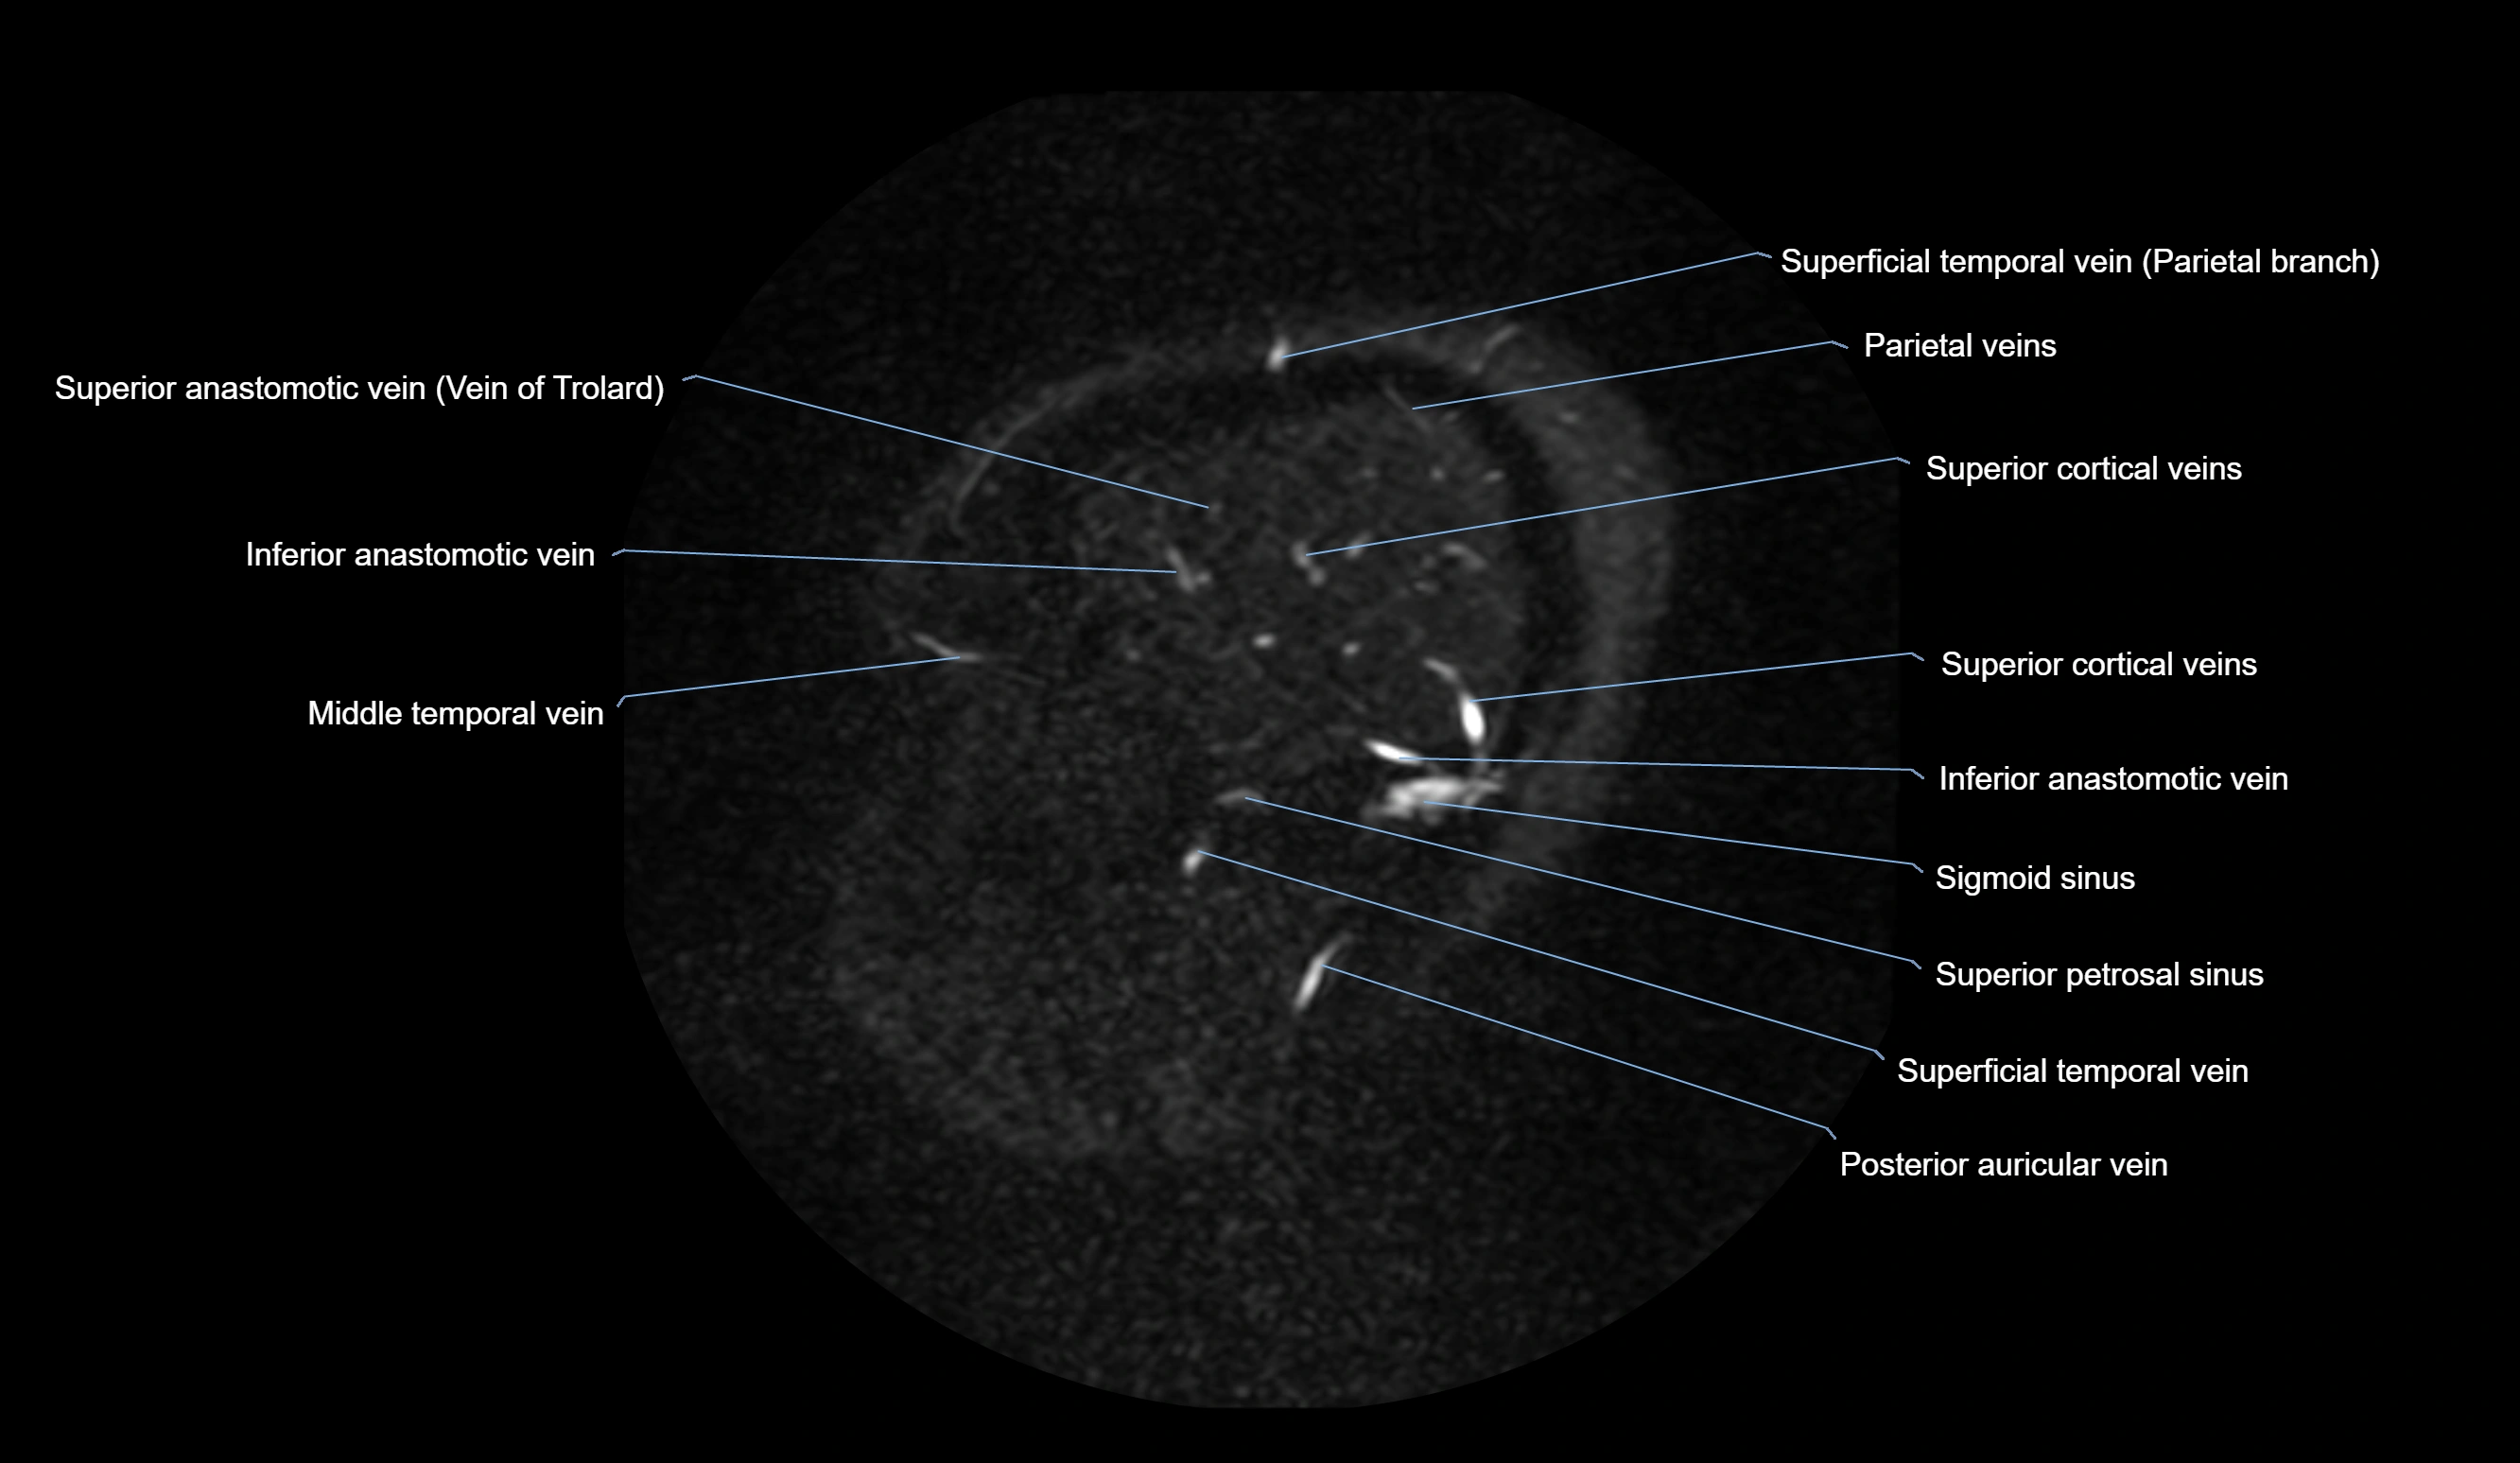

MR Venography (MRV):

• Time-of-flight (TOF) or contrast-enhanced MRV shows the angular vein as a bright enhancing venous channel

• Clearly demonstrates its continuity with the facial vein and superior ophthalmic vein

• MRV is highly useful in evaluating thrombosis, venous obstruction, or collateral venous drainage

MRI images